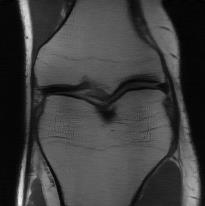

Recently, deep neural networks have greatly advanced undersampled Magnetic Resonance Image (MRI) reconstruction, wherein most studies follow the one-anatomy-one-network fashion, i.e., each expert network is trained and evaluated for a specific anatomy. Apart from inefficiency in training multiple independent models, such convention ignores the shared de-aliasing knowledge across various anatomies which can benefit each other. To explore the shared knowledge, one naive way is to combine all the data from various anatomies to train an all-round network. Unfortunately, despite the existence of the shared de-aliasing knowledge, we reveal that the exclusive knowledge across different anatomies can deteriorate specific reconstruction targets, yielding overall performance degradation. Observing this, in this study, we present a novel deep MRI reconstruction framework with both anatomy-shared and anatomy-specific parameterized learners, aiming to "seek common ground while reserving differences" across different anatomies.Particularly, the primary anatomy-shared learners are exposed to different anatomies to model flourishing shared knowledge, while the efficient anatomy-specific learners are trained with their target anatomy for exclusive knowledge. Four different implementations of anatomy-specific learners are presented and explored on the top of our framework in two MRI reconstruction networks. Comprehensive experiments on brain, knee and cardiac MRI datasets demonstrate that three of these learners are able to enhance reconstruction performance via multiple anatomy collaborative learning.

翻译:最近,深心神经网络大大推进了未经充分取样的磁共振成像(MRI)重建,其中大多数研究都遵循单一解剖一个网络的方式,即每个专家网络都经过特定解剖学的培训和评价。除了在培训多种独立模型方面效率低下之外,这种公约忽视了不同解剖学中共享的、可相互受益的解析知识。为了探索共享知识,一种天真的方法是将各解剖学家的所有数据结合起来,以训练一个全方位网络。不幸的是,尽管存在共享的解析知识,但我们发现,不同解剖学的独家知识可以恶化具体的重建目标,导致总体性能退化。在这项研究中,我们提出了一个新型的深度解剖重建框架,既有解剖学共享知识,又具有具体的解剖学参数,目的是“寻找共同的土壤,同时保留不同解剖学家之间的差异。此外,主要的解剖学学习者将接触不同的解剖学数据,通过多种解剖学重建的模型,并用不同的解剖学研究者将数据展示出一个全方位基础。